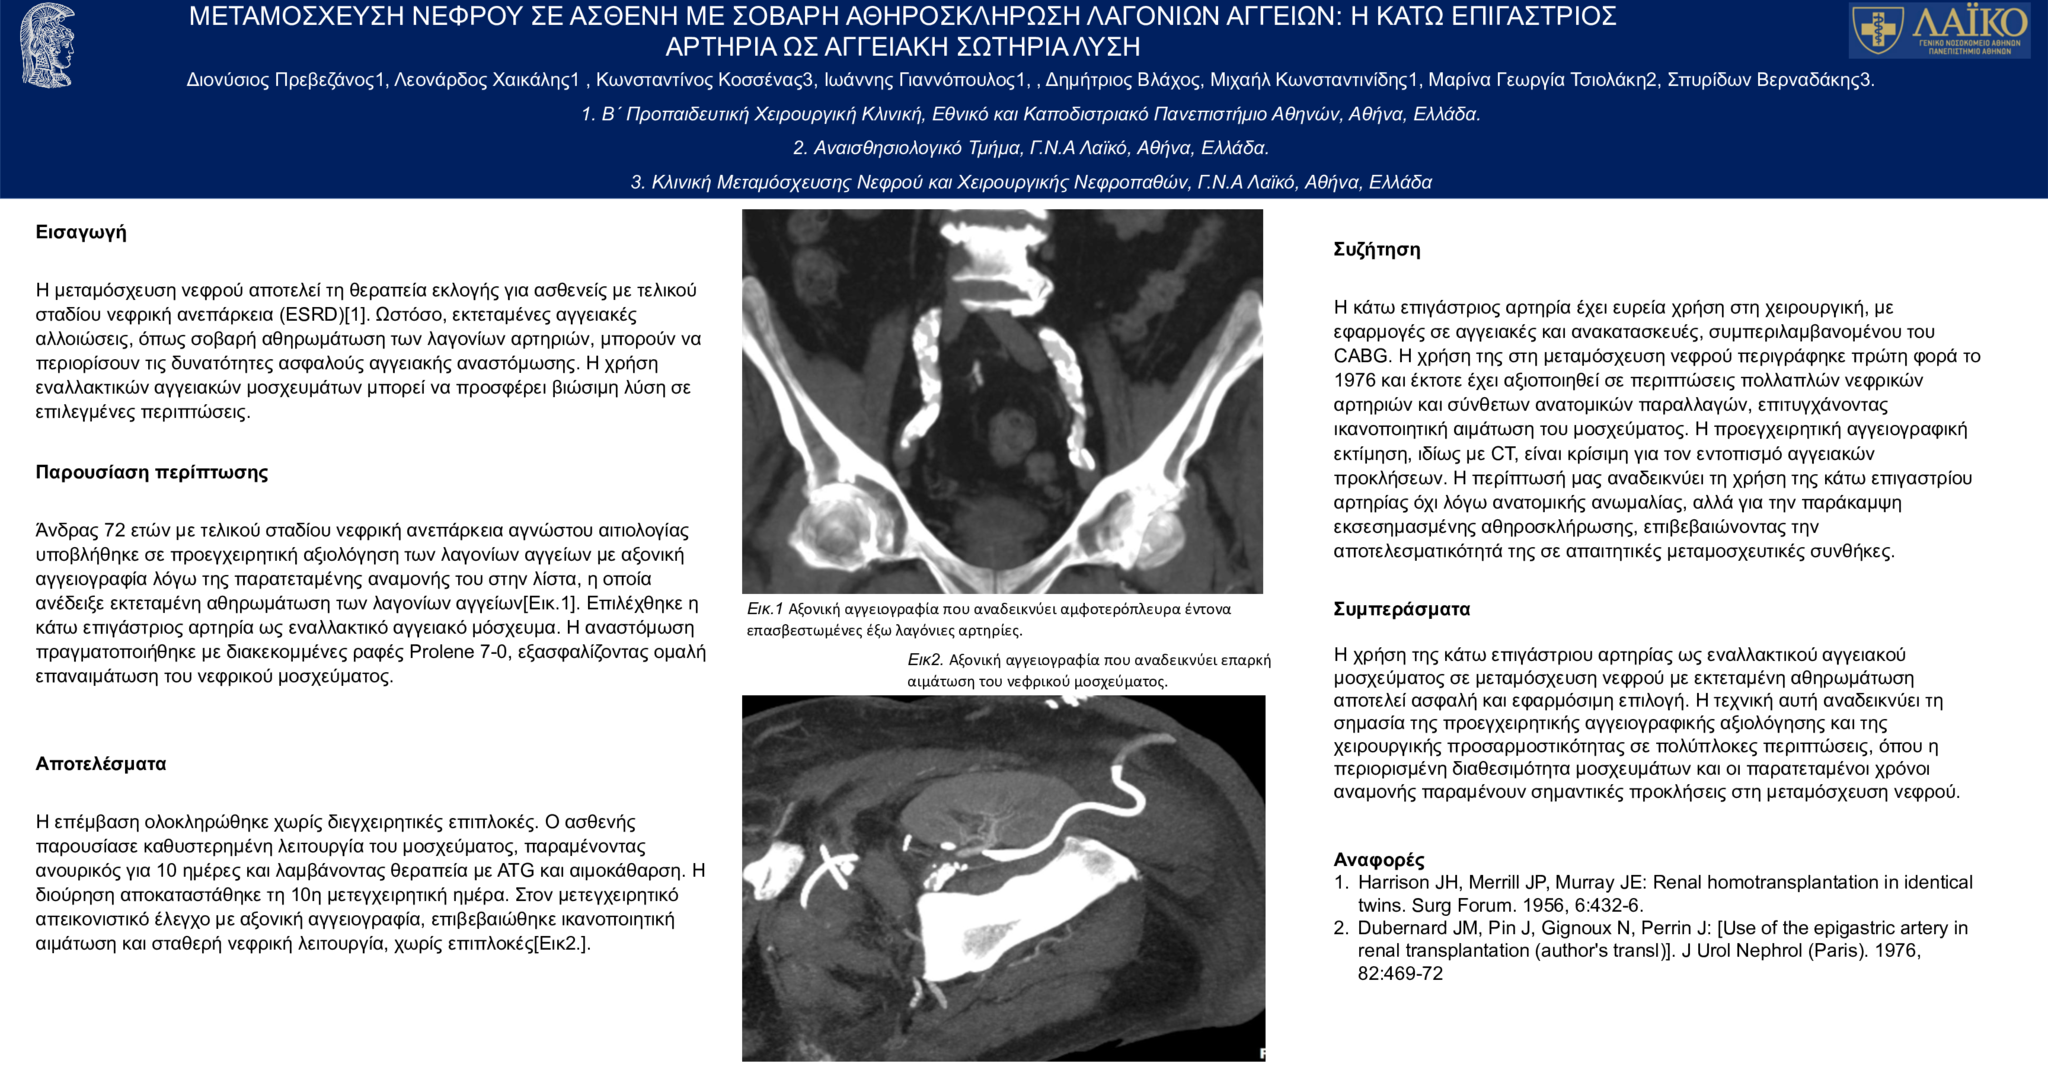

3. ΜΕΤΑΜΟΣΧΕΥΣΗ ΝΕΦΡΟΥ ΣΕ ΑΣΘΕΝΗ ΜΕ ΣΟΒΑΡΗ ΑΘΗΡΟΣΚΛΗΡΩΣΗ ΛΑΓΟΝΙΩΝ ΑΓΓΕΙΩΝ: Η ΚΑΤΩ ΕΠΙΓΑΣΤΡΙΟΣ ΑΡΤΗΡΙΑ ΩΣ ΑΓΓΕΙΑΚΗ ΛΥΣΗ

ΜΕΤΑΜΟΣΧΕΥΣΗ ΝΕΦΡΟΥ ΣΕ ΑΣΘΕΝΗ ΜΕ ΣΟΒΑΡΗ ΑΘΗΡΟΣΚΛΗΡΩΣΗ ΛΑΓΟΝΙΩΝ ΑΓΓΕΙΩΝ: Η ΚΑΤΩ ΕΠΙΓΑΣΤΡΙΟΣ ΑΡΤΗΡΙΑ ΩΣ ΑΓΓΕΙΑΚΗ ΛΥΣΗ